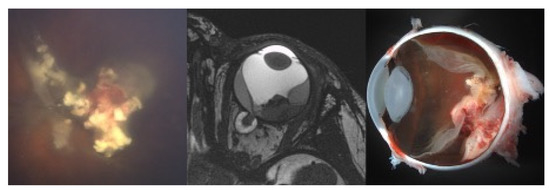

Treatment Technique